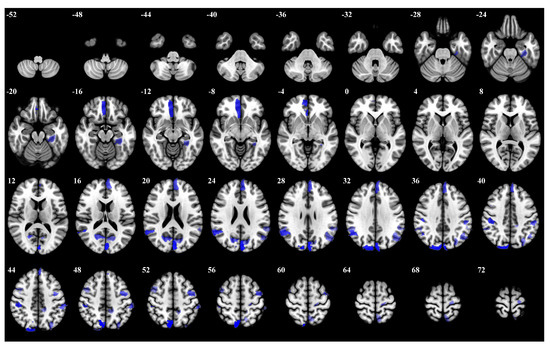

3.1. Importance Weight Characteristics of Brain Regions

| Rank | Brain Regions | Side | Centroid Coordinates (R A S) | Importance Weight |

|---|---|---|---|---|

| 1 | Default Precuneus Posterior Cingulate Cortex 3 | L | −4 −53 20 | 0.246 |

| 2 | Frontoparietal Control Parietal 4 | L | −35 −62 48 | 0.241 |

| 3 | Dorsal Attention Posterior 15 | L | −7 −59 63 | 0.237 |

| 4 | Limbic Temporal Pole 2 | L | 7 42 4 | 0.216 |

| 5 | Dorsal Attention Posterior 8 | L | −46 −29 44 | 0.212 |

| 6 | Frontoparietal Control Parietal 1 | L | −29 −74 42 | 0.211 |

| 7 | Somatomotor 31 | R | 29 −11 65 | 0.206 |

| 8 | Visual 24 | L | −11 −97 17 | 0.195 |

| 9 | Frontoparietal Control Precuneus 2 | L | −5 −64 52 | 0.187 |

| 10 | Dorsal Attention Posterior 13 | R | 35 −36 51 | 0.181 |

| 11 | Limbic Temporal Pole 5 | R | 29 12 −30 | 0.176 |

| 12 | Frontoparietal Control Parietal 5 | L | −42 −52 49 | 0.174 |

| 13 | Dorsal Attention Posterior 5 | R | 32 −66 35 | 0.171 |

| 14 | Default Prefrontal Cortex 10 | L | −53 19 11 | 0.169 |

| 15 | Frontoparietal Control Lateral Prefrontal Cortex 15 | R | 24 10 58 | 0.165 |

| 16 | Frontoparietal Control Temporal 1 | R | 62 −28 −20 | 0.163 |

| 17 | Somatomotor 26 | L | −36 −19 65 | 0.161 |

| 18 | Visual 25 | L | −3 −84 24 | 0.159 |

| 19 | Dorsal Attention Posterior 4 | R | 45 −75 31 | 0.157 |

| 20 | Frontoparietal Control Parietal 2 | R | 56 −41 48 | 0.153 |